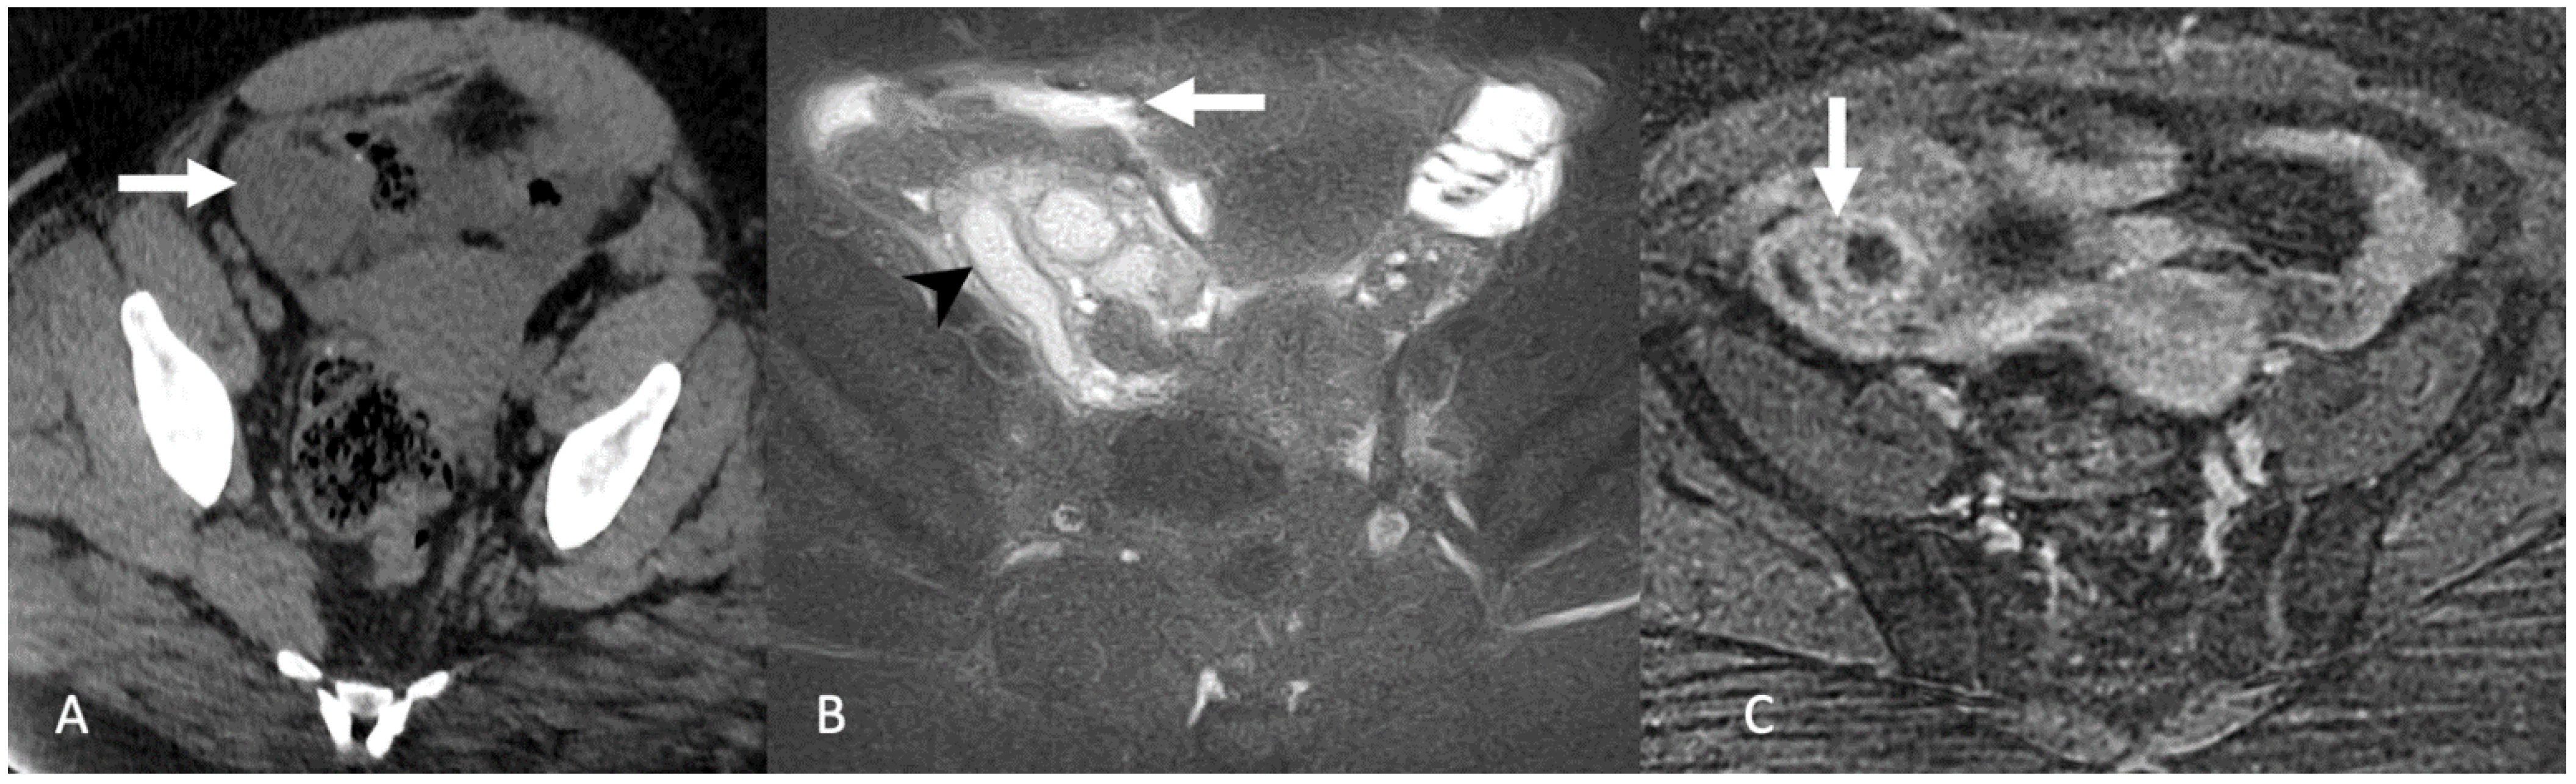

5.1.1. Hydrosalpinx and Hematosalpinx

5.1.2. Pelvic Inflammatory Disease, Pyosalpinx, and Tubo-Ovarian Abscess